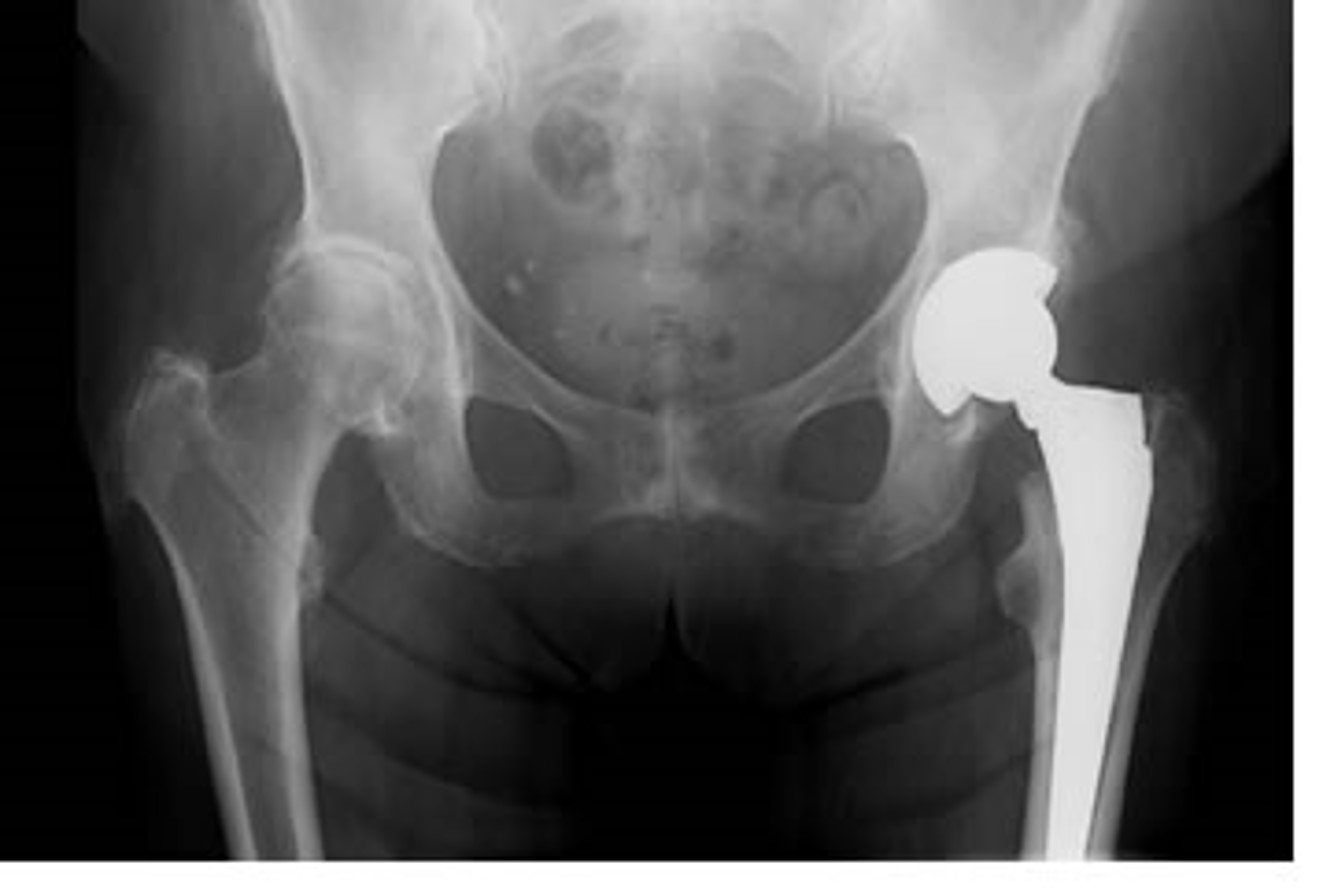

Partial Hip Replacement UnderstandOrtho™